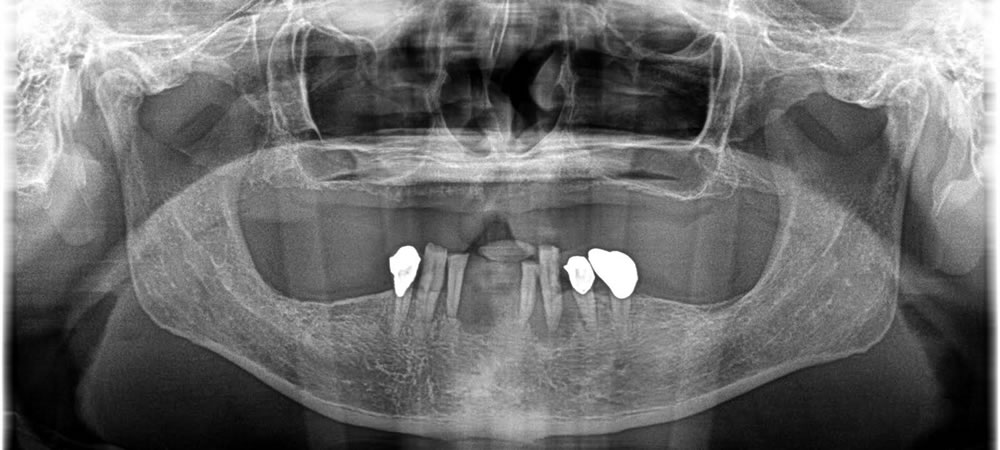

現在残っている歯は全てグラグラに揺れており、検査をしたところ保存する事が困難と診断されました。

抜歯・インプラント埋入手術の実施

歯を抜いて即日インプラント埋入、骨造成を行い、治療用入れ歯を斬感的にセットしました。